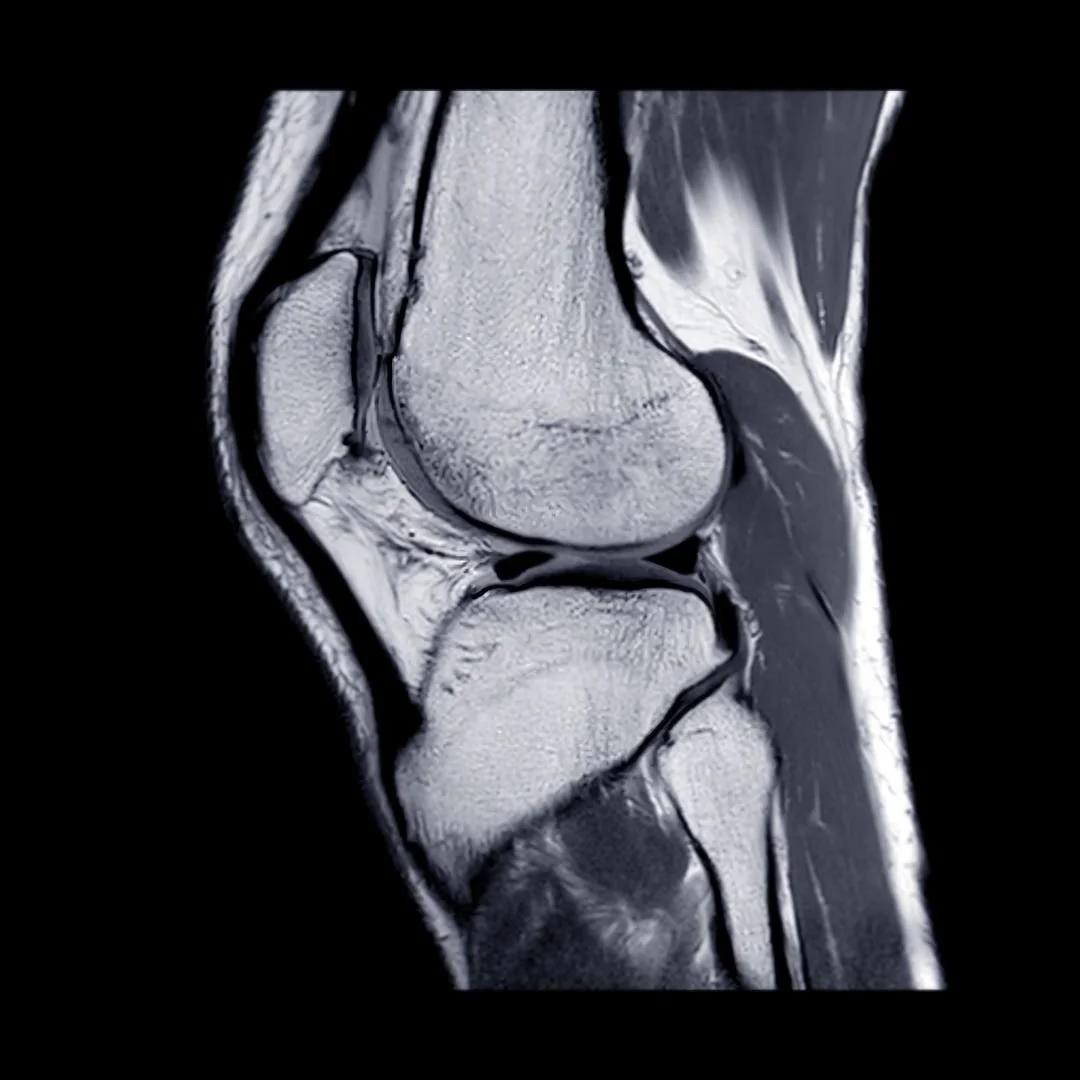

Knee Mensical Injury

Initial trauma in 2010, Bike crash in 2021, Consultant review (MRI) end 2021